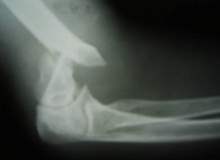

Tenisçi Dirseği

Tenisçi dirseği (lateral epikondilit) dirseğinizi etkileyebilecek birçok aşırı kullanım yaralanmalarından biridir. Tahmin edebileceğiniz üzere tenis oynamak tenisçi dirseğinin sebeplerinden biridir, fakat birçok başka yaygın aktivite de tenisçi dirse